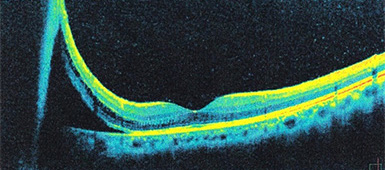

網膜の断層写真で見ると、網膜下に液化硝子体が入り込み網膜が剥がれているのがよく分かります。

網膜断層写真でみると、網膜下液がなくなり網膜が復位しているのが分かります。